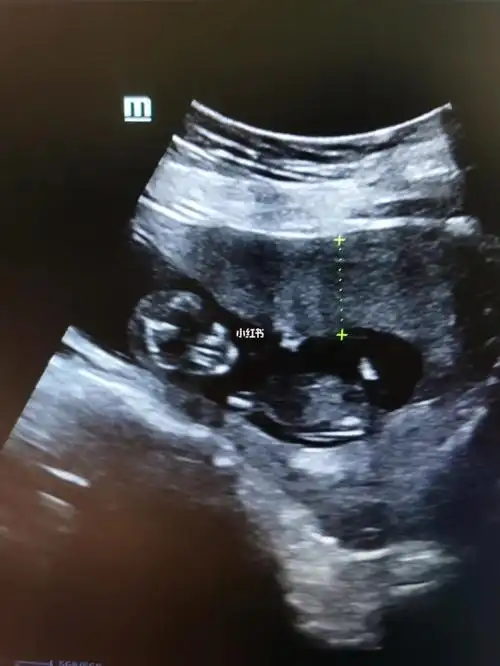

怀孕十四周的胎儿图

怀孕14周胎儿彩超图怀孕14周胎儿图可以看性别吗

孕14周真实胎儿图片14周男孩孕妇有啥感觉